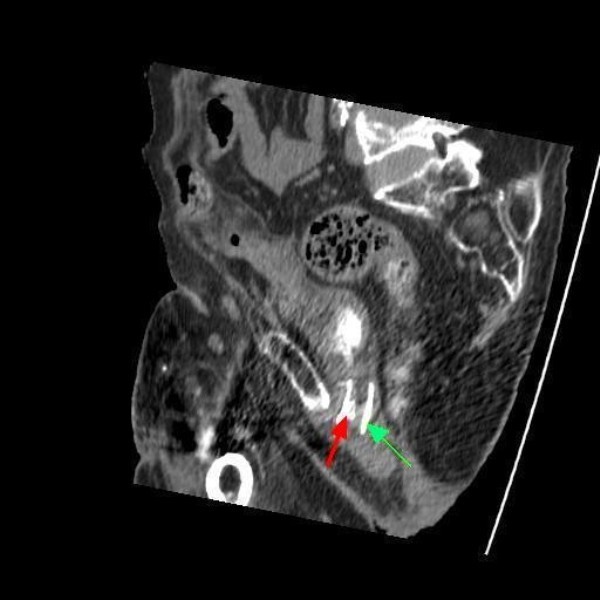

Figure 8From: Lessons we learn from review of urological procedures performed during three decades in a spinal cord injury patient: a case reportComputed tomography of pelvis (24 February 2009): sagittal section shows the stent in its long axis (green arrow) along with a wire protruding into the lumen of stent (red arrow).Back to article page